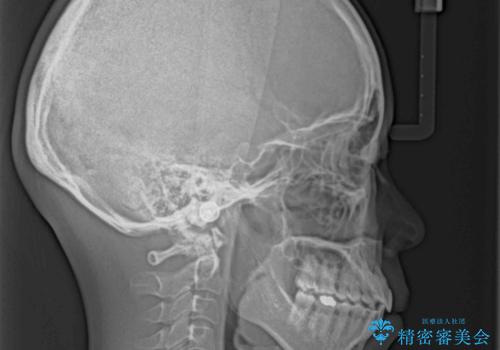

インビザラインによる矯正治療は、受け口傾向の治療に非常に適した方法であり、事前にシミュレーションに沿って治療を進めることできます。

今回の治療では骨格的な偏位があったためアンカースクリューを使用し、より確率の高い治療を行うことができました。